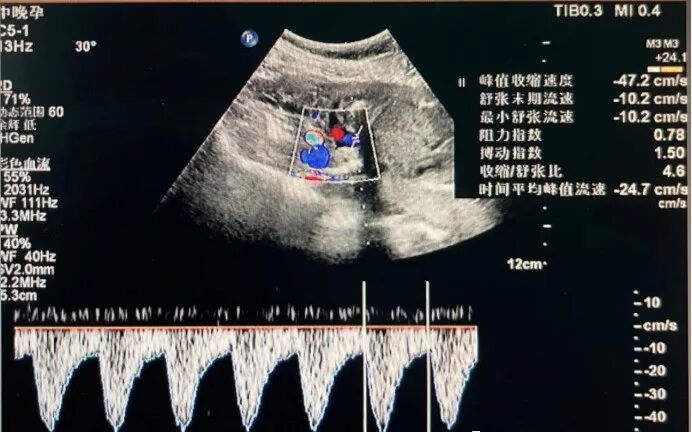

脐动脉S/D值,即收缩期最大峰值流速与舒张末期流速比值,正常情况下胎儿逐渐发育,胎盘也相应增大,血管阻力会逐渐减小,为胎儿的血供和营养提供保障,从孕25周至41周S/D值呈下降趋势。

但孕妈有妊高症、血凝异常及各种原因导致胎儿宫内发育迟缓时,脐动脉S/D值随妊娠周数增加呈上升倾向。

因此,脐动脉S/D值的增高、舒张期血流消失或反向是胎盘发生异常病理改变的重要指征,那应该怎样正确解读呢?

脐动脉S/D值的检查结果如何解读?

脐动脉S/D值升高,提示胎儿可能存在胎儿窘迫、胎儿畸形、胎儿生长受限等情况。

脐动脉S/D值联合胎儿生物物理评分、电子胎心监护、B超等辅助检查,对胎儿畸形、胎儿窘迫、胎儿生长受限等妊娠期疾病的诊断、严重程度判断以及疗效检测有较高的价值。

有时候,胎儿脐带绕颈也会引起此值增高,脐血流S/D值高提示胎儿可能有缺氧,不是说明肯定有缺氧,需要看有没有并发症。